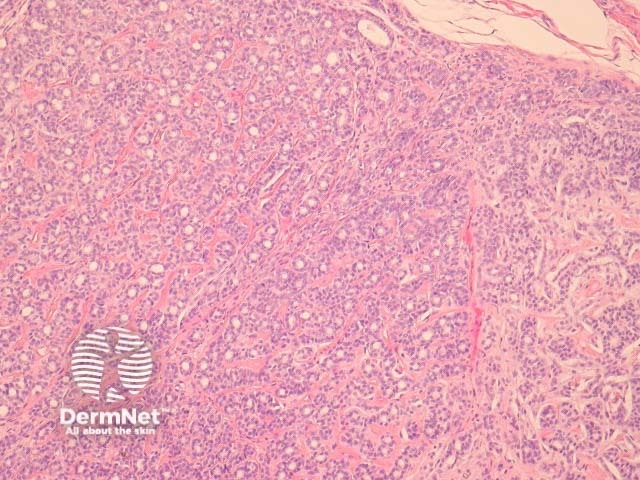

Polymorphous sweat gland carcinoma is a rare adnexal tumour and usually presents as a slow growing dermal mass on an extremity. Local recurrence is not uncommon, particularly following incomplete surgical excisions. Metastasis is rare.

Polymorphous sweat gland carcinomas are dermally based tumours (figure 1) that show a wide range of morphologic growth patterns ranging from solid, tubular (figures 2, 3), cribriform (figure 4) and ductal. Abrupt transitions between morphologies is a characteristic feature (figure 5, 6).

Figure 1